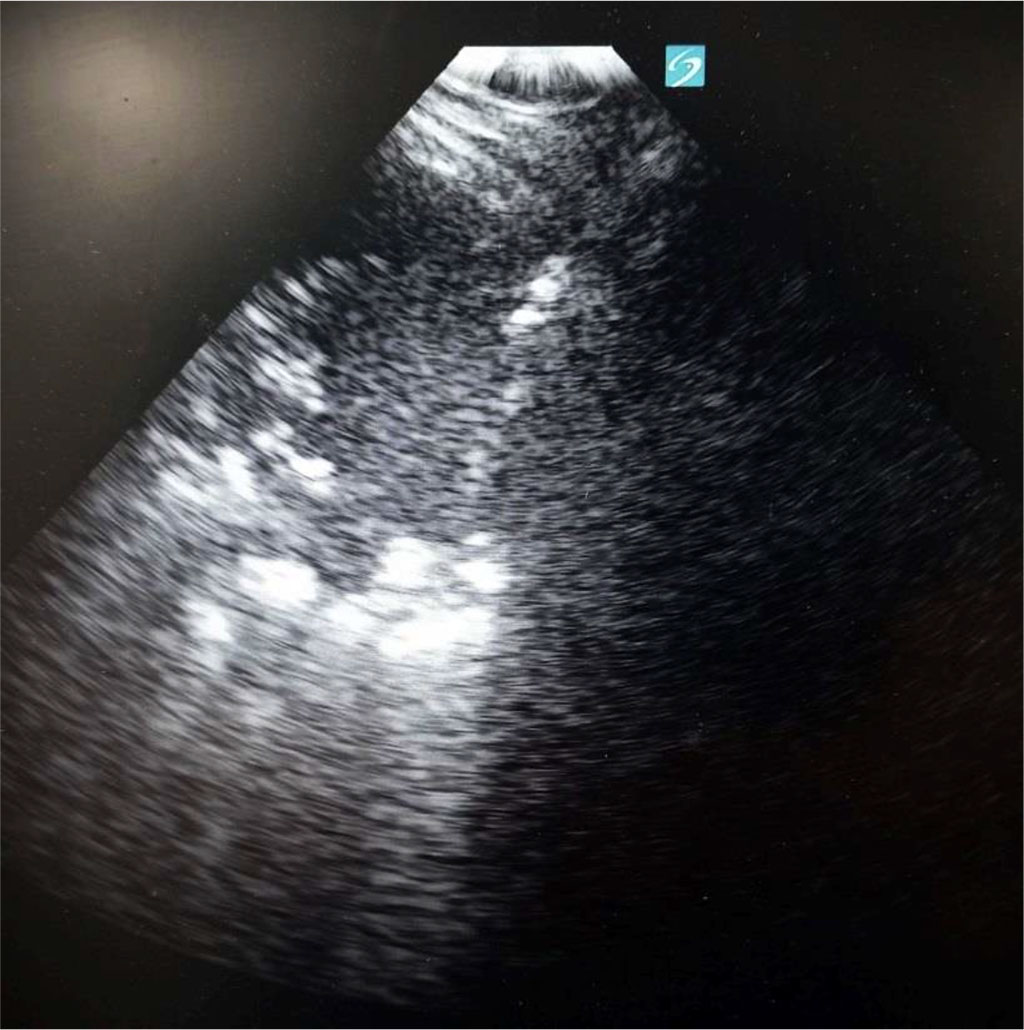

Figure 2. Consolidation with air bronchogram at the left side, diaphragm in the middle and liver at the right side. Author’s private materials.